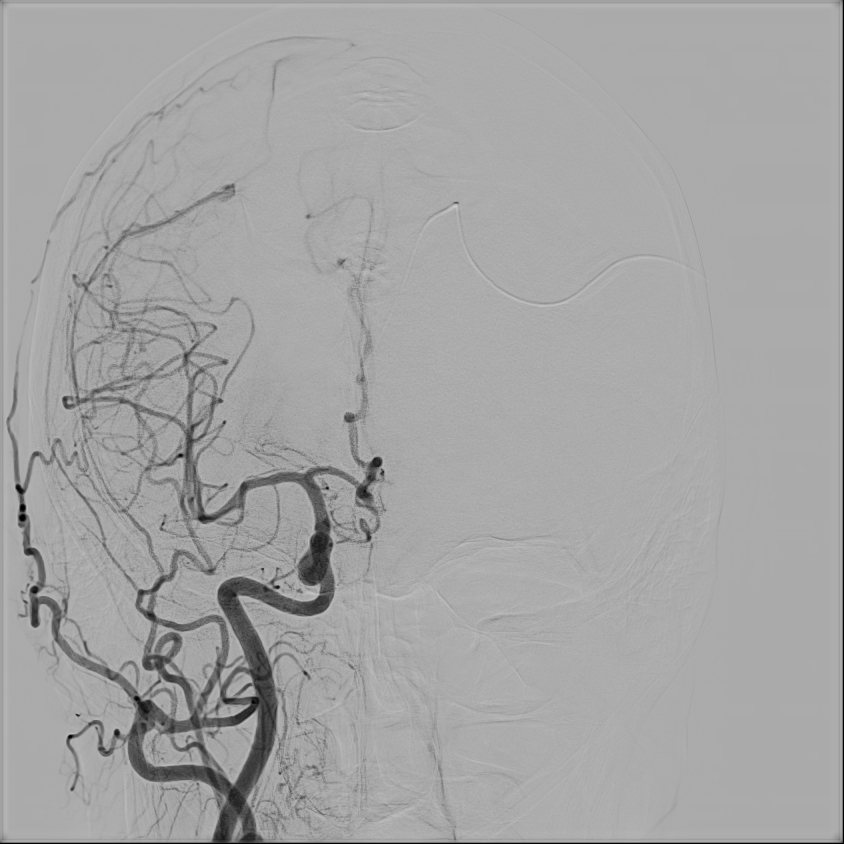

47-letnia kobieta z wywiadem krwotoku z malformacji tętniczo-żylnej (AVM) w prawej okolicy czołowej kilka lat temu, po kilkukrotnej embolizacji zmiany, zarówno w Polsce, jak i w Holandii, została przyjęta do Oddziału z powodu drugiego w życiu krwotoku ze zmiany naczyniowej.

W badaniu angiografii subtrakcyjnej widoczne jest rozległe (ponad 3 cm) gniazdo naczyniowe zaopatrywane z tętnicy przedniej mózgu prawej, zarówno z gałęzi okołospoidołowej, która oddawała 2 tętnice żywiące, jak i gałęzi korowych, oddając jedno naczynie żylne drenujące do zatoki strzałkowej górnej.

W tym przypadku chora została zakwalifikowana do leczenia operacyjnego – kraniotomii czołowej przystrzałkowej i resekcji zmiany naczyniowej. Zmiana została usunięta, bez nowych deficytów neurologicznych. W kontrolnym badaniu DSA nie uwidoczniono resztkowej przetoki naczyniowej, co jest sukcesem operacyjnym.

W dalszym przebiegu hospitalizacji stwierdzono u chorej wodogłowie komunikujące pokrwotoczne, zaimplementowano pacjentce zastawkę komorowo-otrzewnową. Chora została wypisana do domu w stanie ogólnym dobrym, bez deficytów neurologicznych.